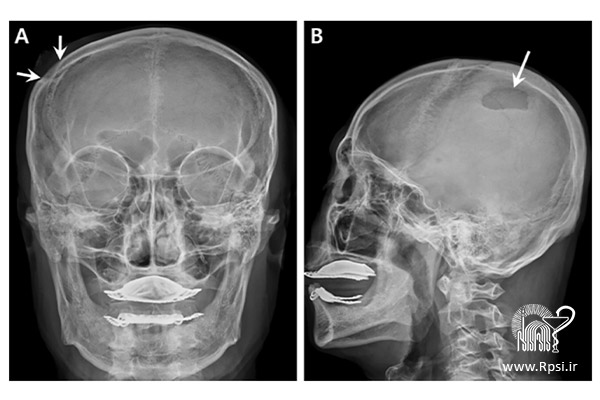

هماتوم پوست سر

● هماتوم پوست سر معمولاً به‌صورت برآمدگی روی سر ظاهر می‌شود. این آسیب به پوست و عضله خارجی وارد می‌شود، بنابراین روی مغز تأثیر نخواهد گذاشت.

هماتوم اپیدورال داخل جمجمه‌ای

● این نوع هماتوم بین صفحه جمجمه و پوشش خارجی مغز رخ می‌دهد.

هماتوم ساب دورال

● هماتوم ساب دورال بین بافت مغز و پوشش داخلی مغز رخ می‌دهد.